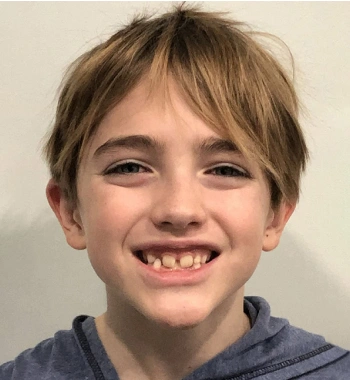

Actual Patient: Alexander

Before

Severe “Underbite”, Narrow Jaws, Adult Teeth Not Growing In

Front View